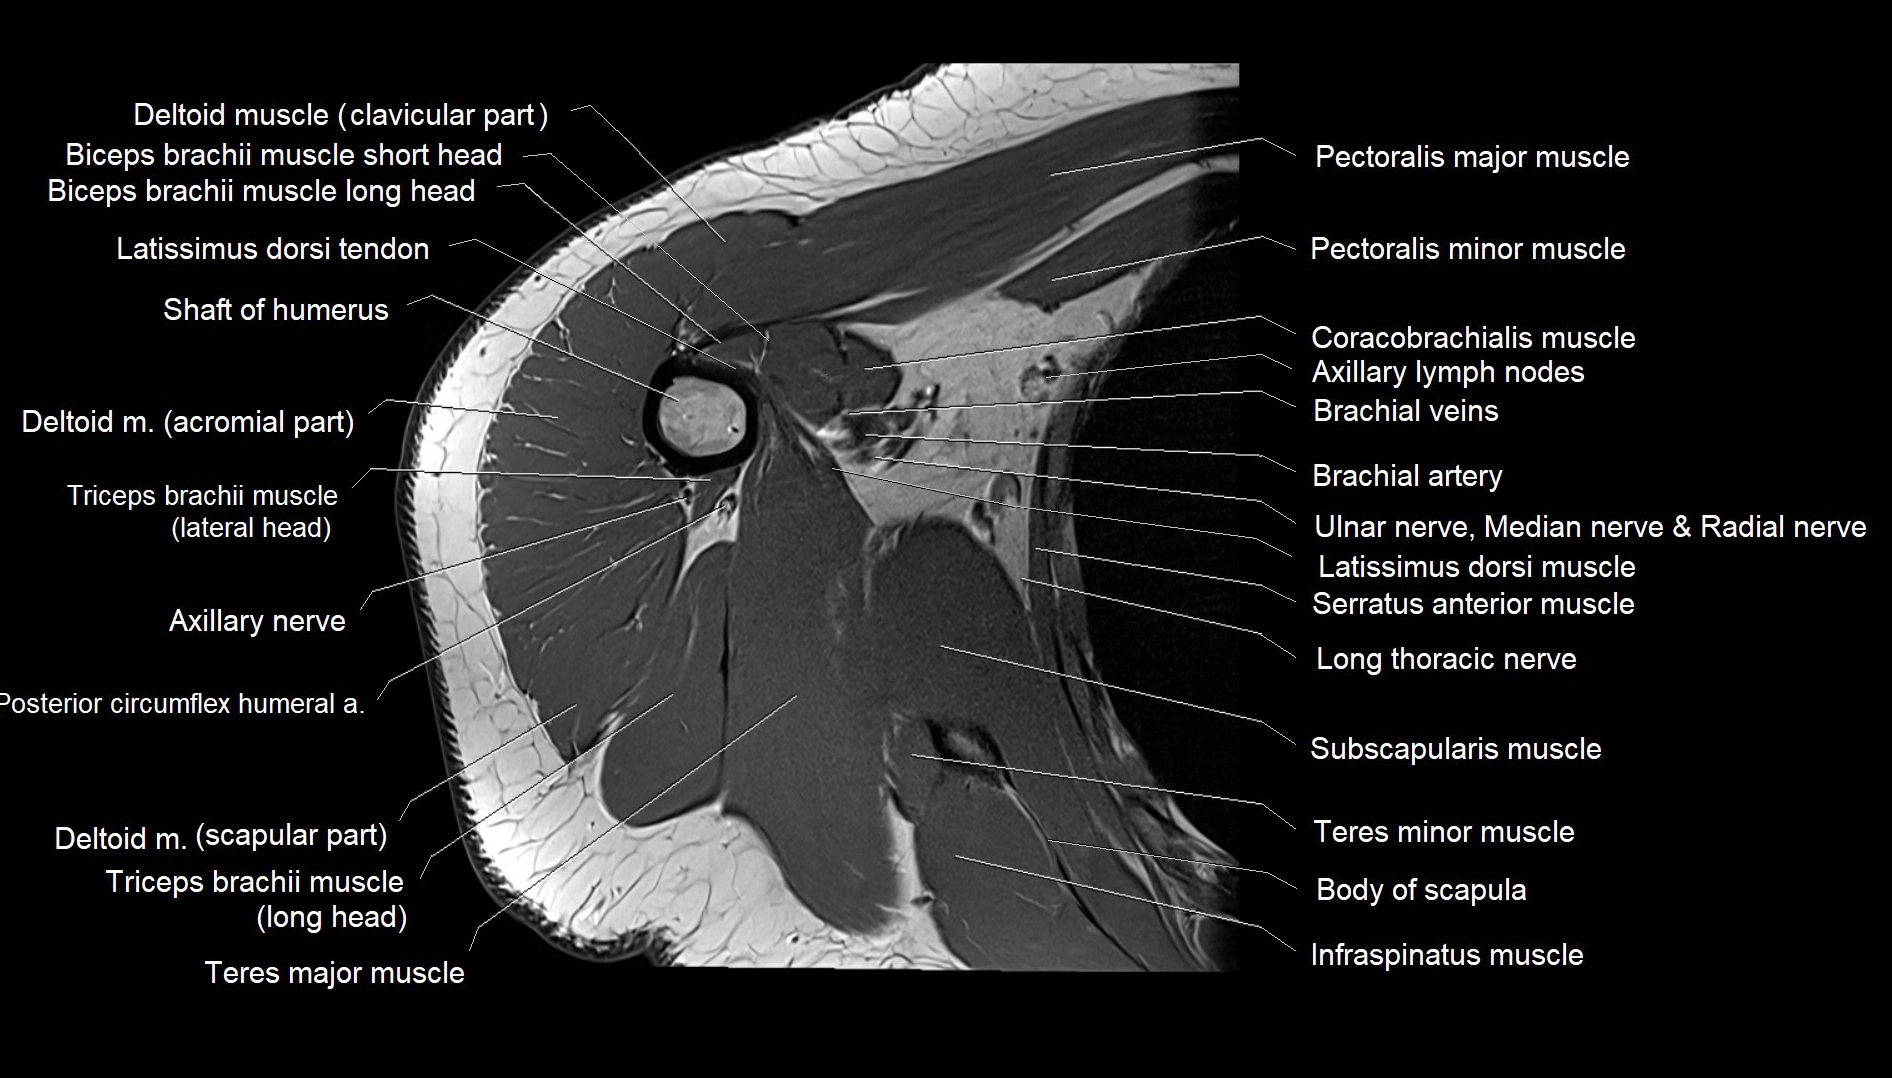

CT image

image